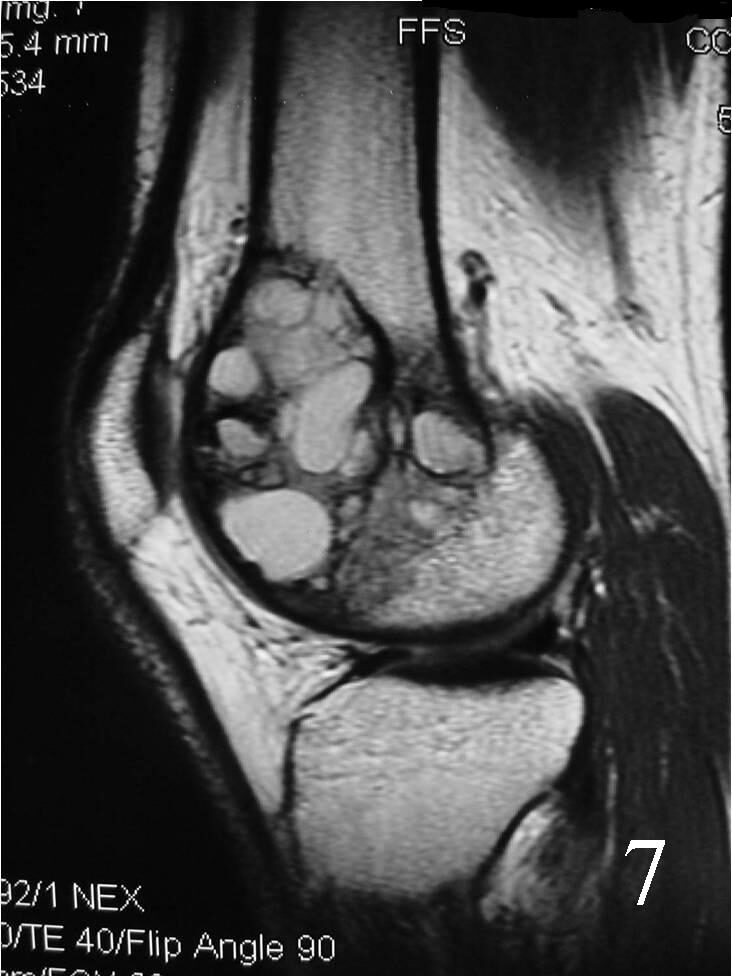

MRI

- Possible fluid-fluid level ( associated with secondary ABC) (Fig. 7, 8)

Fig. 7 Sagittal proton density MRI demonstrates cystic degeneration typical of a GCT